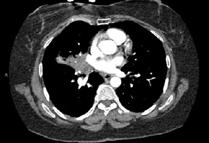

A 58-year-old female with recently diagnosed COVID-19 pneumonia was found to have a dry cough and dyspnoea in the setting of persistent bilateral hilar and mediastinal lymphadenopathy associated with bilateral nodular infiltrates. Of note, she immigrated to the USA from India 10 years prior, with the most recent travel to India 2 years ago. Quantiferon testing upon return to the USA was negative at that time. Workup included bronchoscopy with endobronchial ultrasound revealing non-caseating granulomas with negative stains for acid-fast bacilli (AFB). She was diagnosed with Stage 3 sarcoidosis and initiated on prolonged steroid taper with improvement of symptoms. With taper of steroid dose, however, she developed lymphocyte-predominant exudative effusion with negative cultures, and was reinitiated on a protracted steroid course with rapid symptom resolution. At 4-month follow-up, she had worsening CT findings upon steroid taper, and was started on azathioprine. One month later, she required hospital admission for worsening dyspnoea and fatigue. She was noted to be febrile, tachycardic, and tachypnoeic with worsening

hypoxia. Subsequent CT chest showed progression of bilateral nodular infiltrates with new right upper lobe consolidation and air bronchograms concerning for multifocal pneumonia (Figure 1). Incidentally, she was also noted to have calcified splenic granulomas. She developed rapid clinical deterioration, ultimately requiring mechanical ventilation, pressor support, and continuous renal replacement therapy. Repeat bronchoscopy revealed diffuse alveolar haemorrhage with multiple AFB smears positive for Mycobacterium tuberculosis. She was immediately initiated on quadruple therapy, but unfortunately, despite treatment, developed refractory shock and passed away 2 weeks after initial presentation.

A) Initial adenopathy with peripheral patchy ground glass opacities in the right lung following COVID-19 pneumonia. B) Persistent bulky adenopathy 1 year after initial presentation. C) Extensive nodularity throughout the right lung with increasing confluent opacities in the right upper lobe and stable mediastinal lymphadenopathy 2 years after initial presentation. D) Tuberculosis superimposed on sarcoidosis with progression of nodular infiltrates, worsening right upper lobe consolidation, and air bronchograms with incidental calcified splenic granulomas (not pictured).

Figure 1: CT progression of patient’s sarcoidosis and tuberculosis.